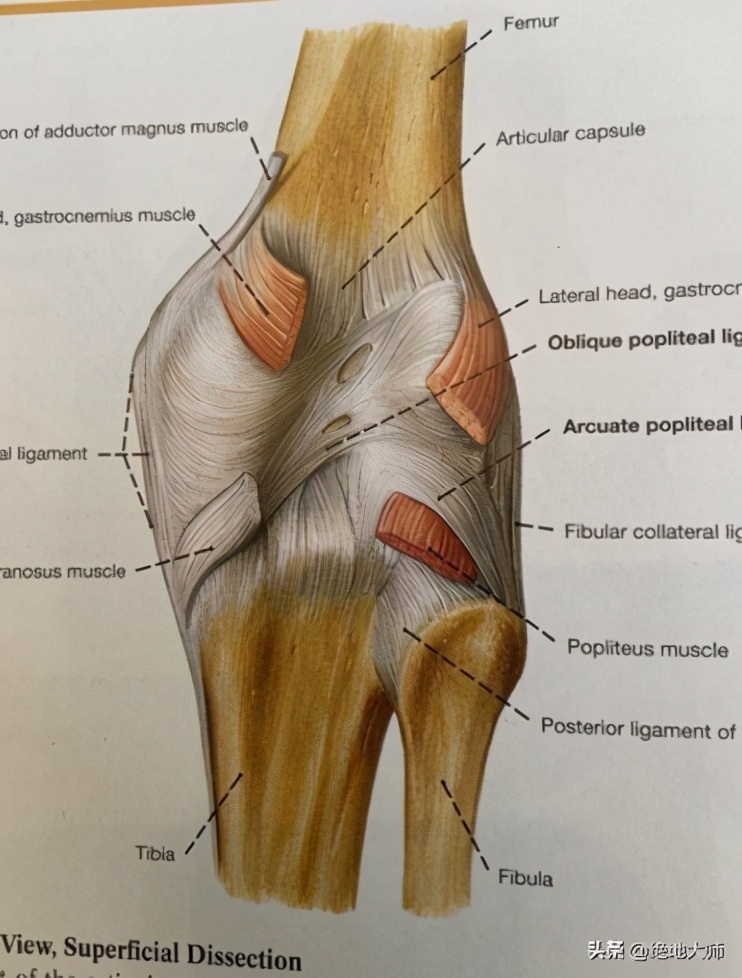

10. ANATOMY: MUSCLES 解剖:肌肉

TENSOR FASCIA LATTE 阔筋膜张肌(臀中肌抑制)

POPLITEUS, GASTROCNEMIS 腘肌、腓肠肌

11. ANATOMY: POPLITEUS/VMO MUSCLES 解剖:腘肌/VMO肌